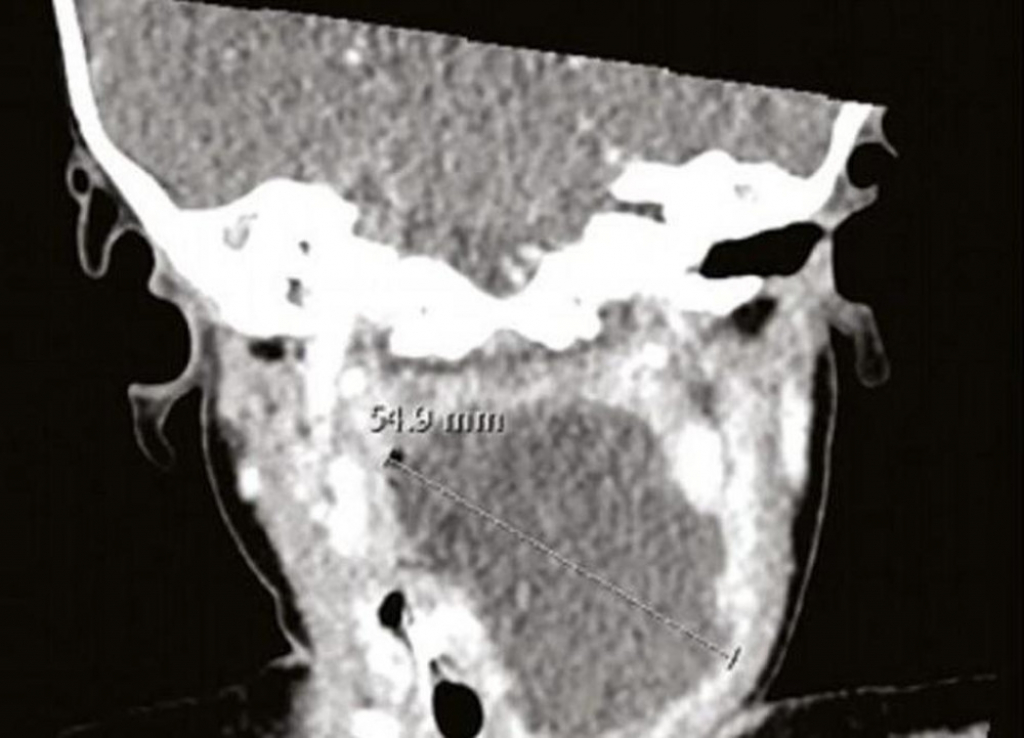

- Dijagnostikovali su joj bronhiolitis te je sledeća tri dana dobijala terapiju, a potom su je opet poslali kući. Međutim, vratila se ponovo šest dana sa istim simptomima, pa su odlučili da joj snime vrat - pišu u časopisu doktori Paul Heyworth i Ryan Shulman. Tek tada otkrili su što joj je - u grlu se stvorio apsces, gnojna nakupina oko zvezde petokrake. Devojčicu su hitno odveli na operaciju kako bi uklonili zvezdu i gnoj, a malena se potom dobro oporavila.